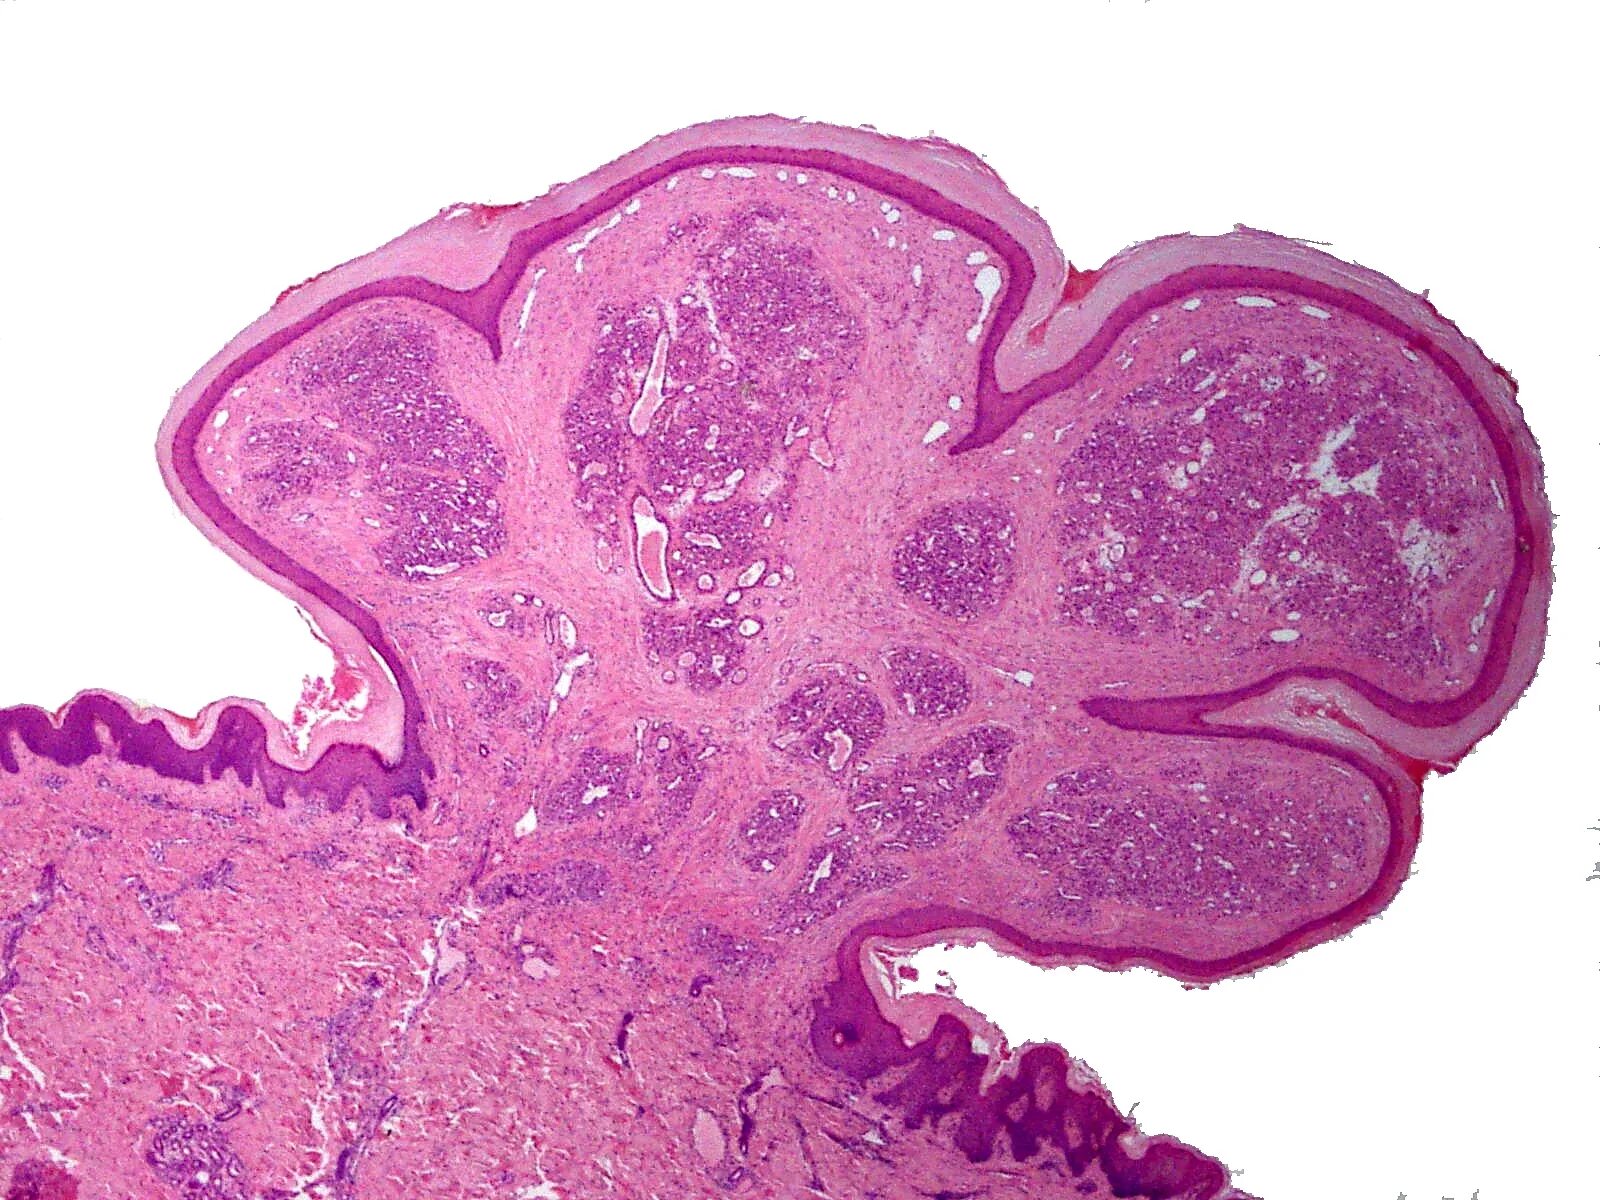

Папиллома гистология